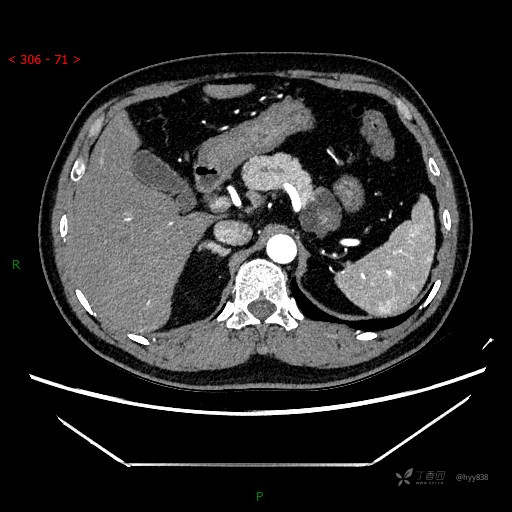

腹部CT平扫